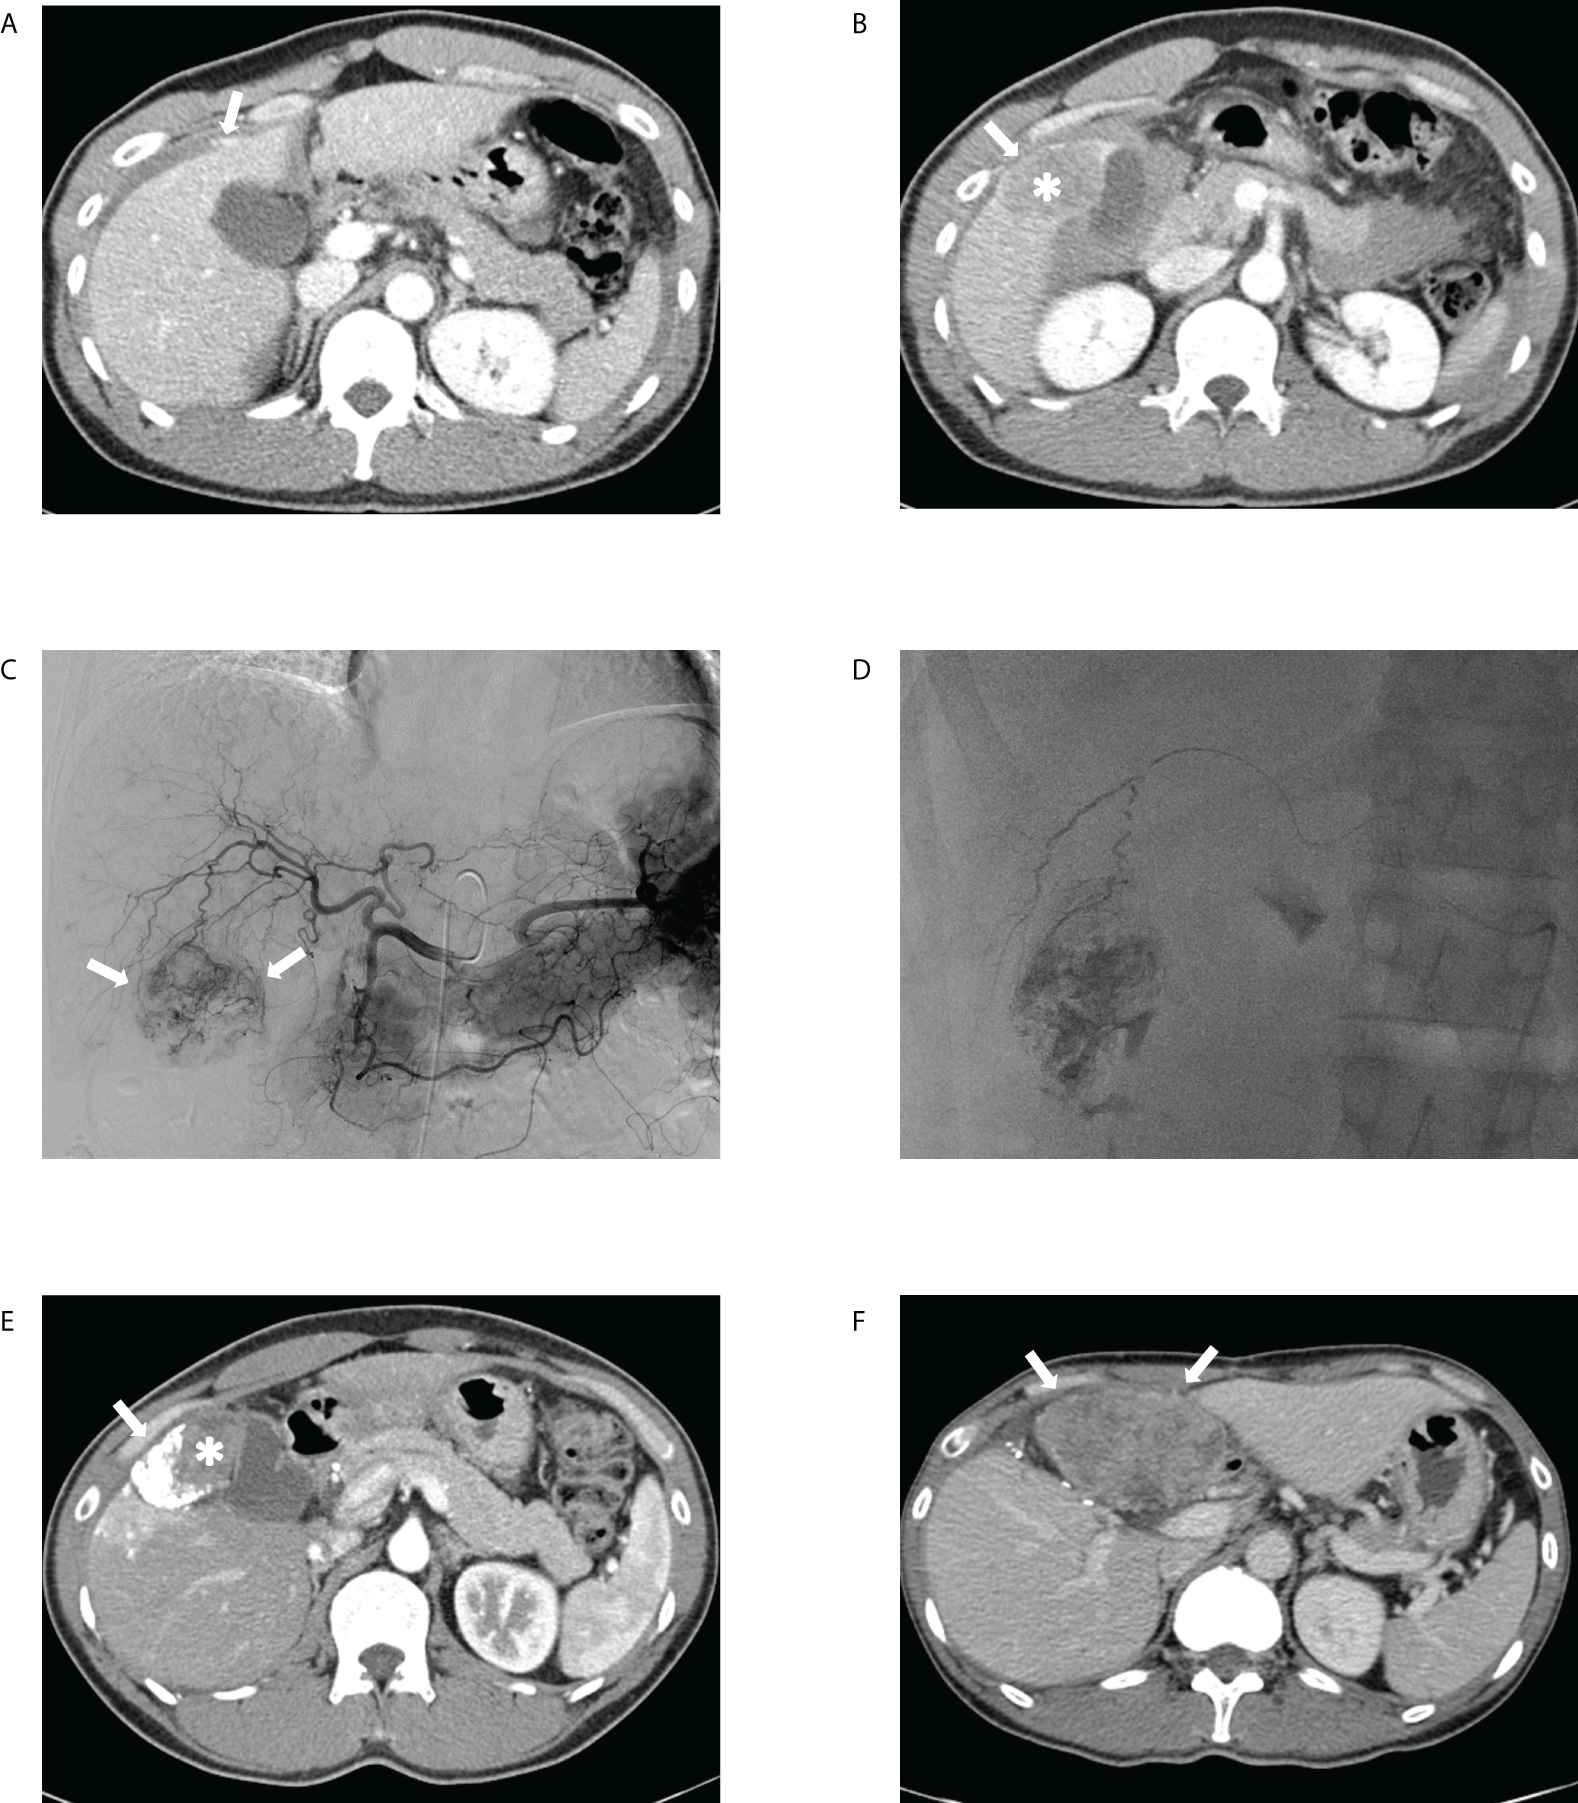

Figure 5

Transcatheter arterial chemoembolization (TACE) performed for ruptured hepatocellular carcinoma in a 41-year-old male patient. The portal phase of the initial computed tomography (CT) demonstrates (A) contrast media extravasation (arrow) from the tumor to the peritoneum and (B) washout lesion (asterisk) in segment 6 of the liver protruding to the peritoneum with focal discontinuity (arrow) of the liver surface, suggesting ruptured hepatocellular carcinoma. (C) Celiac angiography showing hypervascular tumor staining (arrows) corresponding to the CT findings. (D) Spot image of fluoroscopy demonstrating administration of iodized oil-doxorubicin mixture at the branch of S6 with partial uptake within the tumor. (E) Portal phase of the 1-month follow-up CT shows lipiodol-doxorubicin uptake (arrow) in the lateral aspect of the index tumor with a residual lesion (asterisk) in the medial portion. (F) Portal phase of the 11-month follow-up CT after tumorectomy performed at 6-month demonstrates a huge hypoattenuating mass (arrows) in the peritoneum, suggesting intraperitoneal drop metastasis.